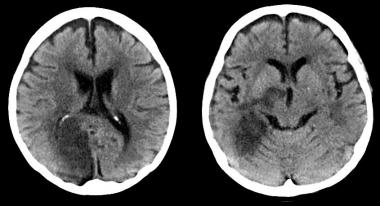

Efectos cerebrales del control intensivo de la hipertensión arterial

En un subestudio del SPRINT se encuentra que los niveles más bajos de presión arterial se asociaron a una pequeña disminución de lesiones de la sustancia blanca, de significación clínica incierta. JAMA 13 de agosto de 2019